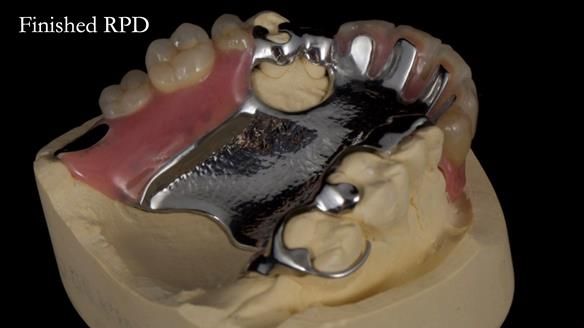

Keith’s case was one of the most challenging and rewarding cases I’ve treated this year. This 64 year old man presented with ill-fitting acrylic partial dentures that lacked stability, retention, and aesthetics. They constantly broke. He had lost the upper front teeth in a road traffic accident in his early 20s. The unopposed teeth had erupted, taking up space. After careful planning, we made a durable, metal-based upper partial denture/splint to address his dental concerns. He loved the outcome.

1. Denture design: A custom cobalt-chromium framework was Scandinavian-designed to maximise stability, protect the remaining teeth, and allow for future additions if needed.

Keith’s denture incorporated a Duracetal shell clasp on upper right first premolar (Myerson), which are designed to be virtually visible, providing a more aesthetic solution while enhancing patient comfort. The Scandinavian-inspired approach, based in modern removable prosthodontic techniques, ensured the denture was not only durable but also visually pleasing. Additionally, the design was carefully planned to allow for future modifications, ensuring that if Keith loses additional teeth, the denture can be adapted rather than replaced entirely.